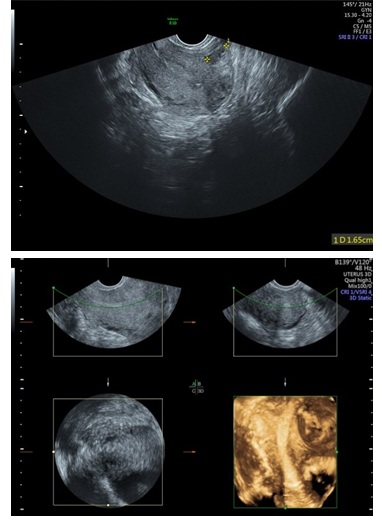

Figure 4: 2D & 3D USG showing Adhesions in Left Cornua of Uterine Cavity (Asherman Syndrome).

Hysteroscopy showing Adhesions in Left Cornua of Uterine Cavity (Asherman Syndrome). Left Ostia is obscured due to adhesions.

In a similar study Haemila et al., [10] in a study of females with premenopausal bleeding found that 3D TVS detected myomas in 14 (20%), polyps in 8 (11.43%), and endometrial mass in 1 while hysteroscopy detected myomas in 6 (8.57%), polyps in 11 (15.72%) and endometrial mass in 1 (1.43%). In contrast to the study above, we found that 3D TVS detected 20% abnormalities, out of which 15 (7.5%) were endometrial polyps, 6 (3%) were submucous myomas, 6 (3%) were septa, 1 (2%) were adhesions, and 5 (2.5%) was unicornuate uterus. While hysteroscopy detected 32.5% abnormalities, out of which 28 (14%) were polyps, 7 (3.5%) were submucous myomas, 5 (2.5%) were septa, 5 (2.5%) were adhesions and 5 (2.5%) were unicornuate uteruses. In our study, 3D-TVS failed to detect 13 (36.45%) cases with endometrial polyps, which were detected on hysteroscopy.

Our study demonstrated that 3D TVS had high specificity, but its sensitivity was limited, especially for detecting endometrial polyp. A significant percentage of patients had evidence of uterine cavity pathology. As such, hysteroscopy remains the preferred procedure for accurate detection and diagnosis of uterine cavity lesion.